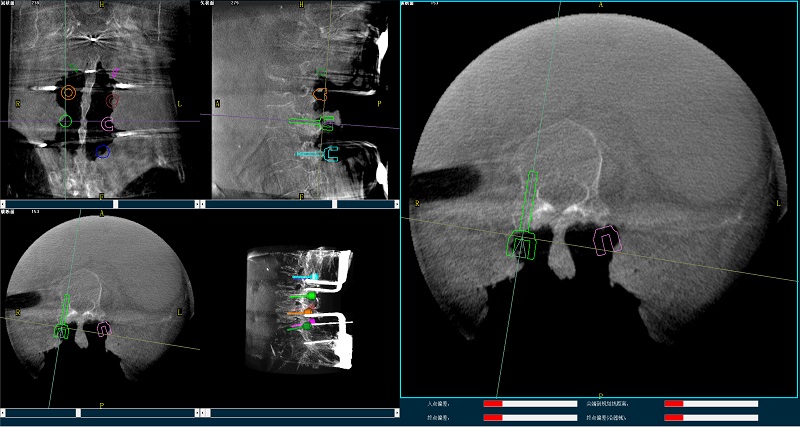

三維圖像

(2)使用普愛(ài)醫(yī)療平板三維C形臂掃描患者,得到術(shù)中三維圖像并傳送至骨科機(jī)器人導(dǎo)航系統(tǒng)。骨科機(jī)器人導(dǎo)航系統(tǒng)基于高清術(shù)中三維圖像進(jìn)行手術(shù)規(guī)劃。

手術(shù)規(guī)劃圖像